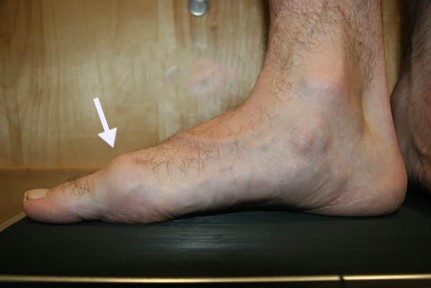

Foot With Hallux Rigidus

Patients with hallux rigidus often develop a bump on the top of the foot at the base of the big toe (white arrow).